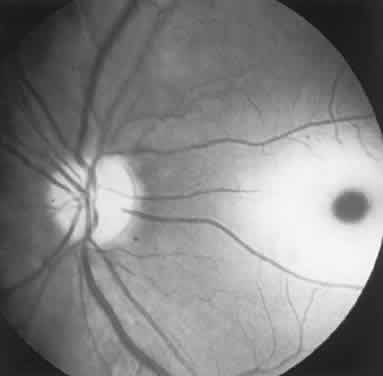

Diseases and pathologic alterations involving the retina provoke the least clinical dilemma in that, for the most part, the ophthalmoscope resolves the question of the anatomic level at which the visual pathways are involved. The problem of complicated neurodiagnostic studies should not arise, although fluorescein angiography, electroretinography (ERG), and other retinal function tests (see Volume 2, Chapter 2) may prove valuable. There are two major pitfalls to be avoided. First, minimal retinal changes may be misconstrued as the cause of disproportionately perturbed visual function, or a normal macula may be misinterpreted as abnormal. For example, a patient with relentless monocular visual loss, a central field depression, and afferent-defect pupil, with a few drusen or minimal derangement of retinal pigment epithelium at the fovea, must not be dismissed with an inappropriate diagnosis of “macular degeneration.” In this instance, the afferent-defect pupil indicates a conductive lesion of the optic nerve and cannot be attributed to minimal retinochoroidal disease. Second, true macular disease, especially when bilateral and ophthalmoscopically subtle, should raise the question of macular dystrophies that masquerade as neurologic disease or for which no cause is apparent (Fig. 1). Indeed, there are increasing numbers of retinal disorders that produce subtle or even insignificant objective fundal changes that may escape conventional ophthalmoscopic detection.

Fig. 1. A 14-year-old boy referred for occult neurologic disease or malingering who had undergone magnetic resonance imaging and psychiatric counseling. Visual acuity was 20/100 in both eyes. Fundi (A and B) show thinned rounded macular reflexes and mild pigment changes at the foveae. Fluorescein angiography (C) disclosed marked macular pigment epithelial disturbance. Diagnosis: juvenile macular degeneration (Stargardt's type).